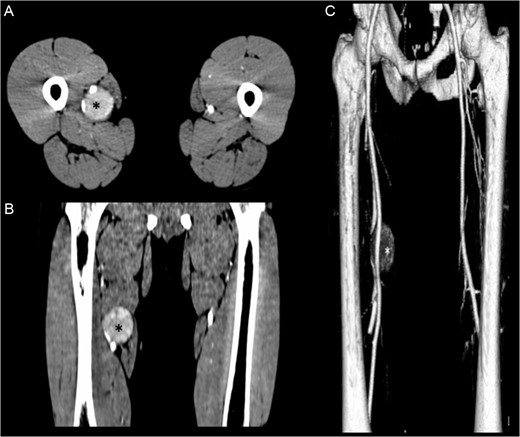

(A, B) Contrasted-enhanced CT scan shows a 4.1 × 4.3 × 4.6-cm mass (*) adjacent to the neurovascular bundle of the right thigh. (C) 3D reconstruction of the CT scan shows the displacement of the right femoral artery.